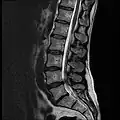

Position of human lumbar vertebrae (shown in red). It consists of 5 bones, from the top down, L1, L2, L3, L4 and L5.